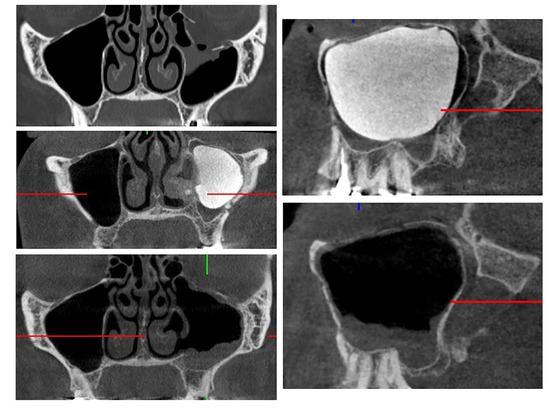

2.5. Geometric Measurements